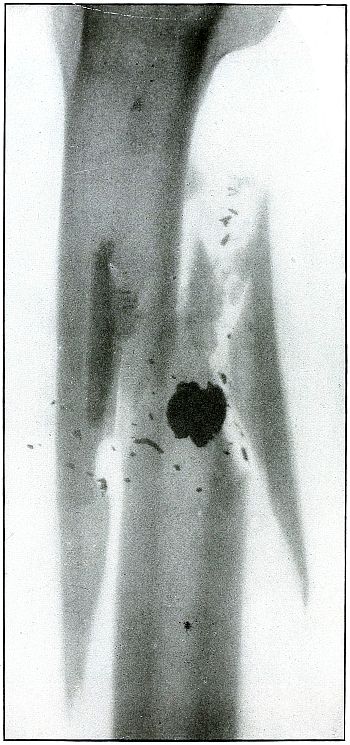

Gunshot Fracture of the Middle of the Tibia,

with Lodgment of the Missile.

The course of the bullet was transverse, from without inward, striking on the side of the shaft of the tibia.

The bullet was so badly damaged by ricochet that only a portion of it was the cause of this wound.

The range was short, if not close, as the missile after striking a resisting object with force enough to break itself retained enough energy in a fragment of less than half its mass to cause a long fissure fracture, with the separation of smaller fragments.

The treatment is noninterference, except for infection, which, contrary to what might be expected from presumable contamination from the object from which it ricocheted, does not occur more frequently in ricochet than direct wounds with lodgment of the projectile. [Pg 144]

Plate 67.

_